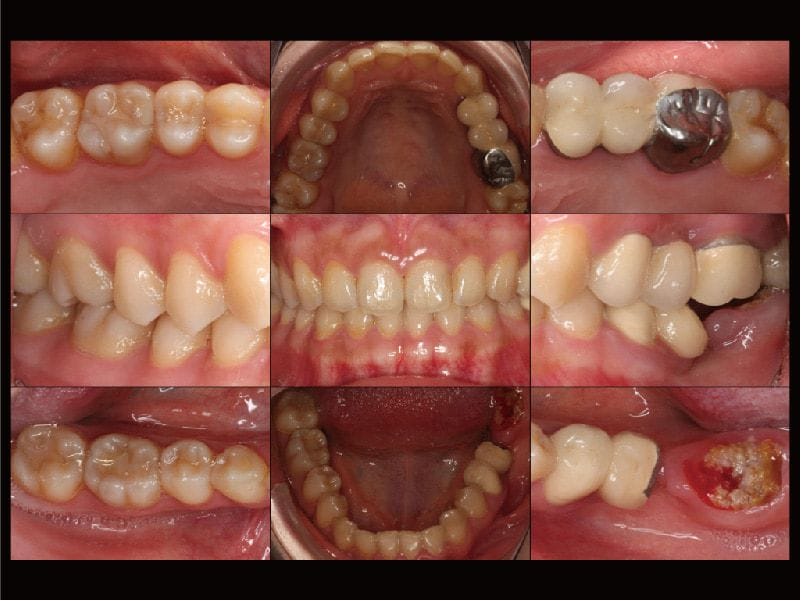

圖示:牙周病治療前,各角度口腔牙齒近照有助於進行更全面、更完整的檢查與診斷

Miss Sung 在牙周方面,雖然本身沒有什麼主觀的症狀,但還是有部分區域有比較深的牙周囊袋,與初期的齒槽骨流失。特別在左上後牙區也是有一組密合度已經不甚理想的假牙,容易造成牙菌斑或牙結石的殘留,屬於牙周病風險比較高的區域。

圖示:主訴患處和左上牙橋,都有牙齦發炎紅腫的狀況

Miss Sung 被診斷為全口輕度牙周病,通常經過 第一階段牙周病治療 後,就能有還不錯的效果。另一個我們重視的事情就是在治療期間,一定要關心她口腔衛教改善的狀況,唯有養成良好的口腔居家照顧習慣,才能增加植牙的成功率,這樣才能將未來惱人的『植體周圍炎』的機率降到最低,並且也延長其他自然牙的壽命。